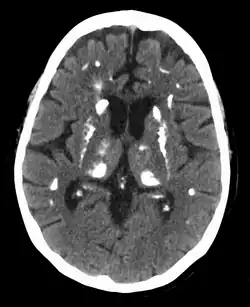

Common manifestations of hypercalcemia include constipation, vomiting, weakness, lethargy, fatigue, depression, bone pain, muscle soreness (myalgias), joint pain, decreased appetite, feelings of nausea, abdominal pain, pancreatitis, polyuria, polydipsia, cognitive impairment, kidney stones ([nb 1]), vertigo and osteopenia or osteoporosis.[10][11] A history of acquired racquet nails (brachyonychia) may be indicative of bone resorption.[12] Radiographically, hyperparathyroidism has a pathognomic finding of rugger jersey spine.[13] Parathyroid adenomas are very rarely detectable on clinical examination. Surgical removal of a parathyroid tumor eliminates the symptoms in most patients.

Hyperparathyroidism can cause hyperchloremia and increase renal bicarbonate loss, which may result in a normal anion gap metabolic acidosis.[32] ALP level can be elevated due to bone turnover. Additionally further tests can be completed to rule out other causes and complications of hyperparathyroidism including a 24-hour urinary calcium for familial hypocalciuric hypercalcemia, DEXA scan to evaluate for osteoporosis, osteopenia, or fragility fractures, and genetic testing.[33][34][35][36] Additionally a CT scan without contrast or renal ultrasound can be done to assess for nephrolithiasis and/or nephrocalcinosis if there is concern for it.[36]